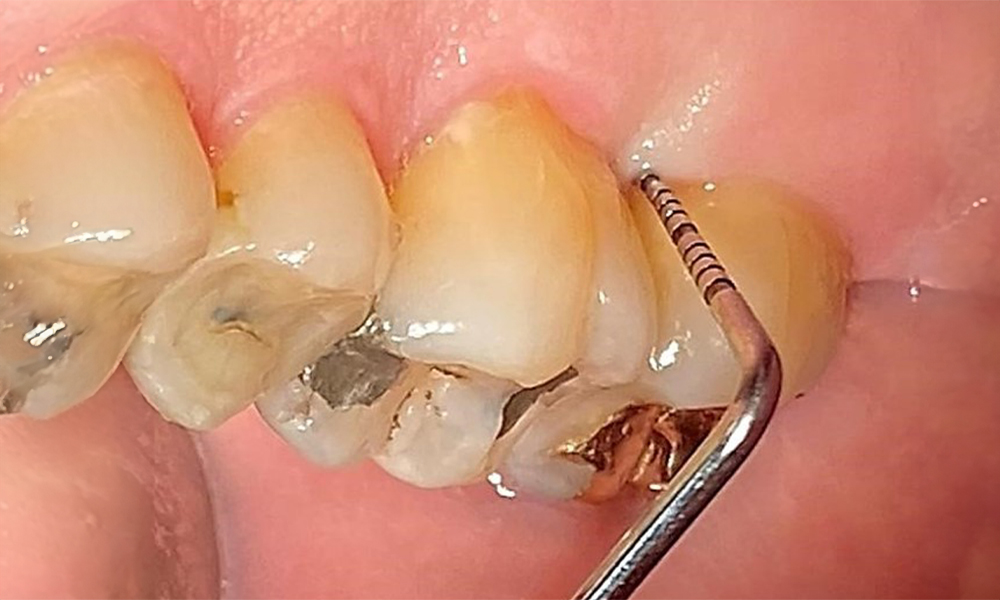

The patient has a full dentition with 28 teeth, which includes amalgam and composite fillings in the molar and premolar regions. There is a visible clinical marginal gap present on tooth 14. Tooth 27 has an adequate gold inlay. There are also generalized attritions and abrasions. (Fig. 2, Fig. 3, Fig. 4, Fig. 5, Fig. 6)

The patient has stage II, grade B periodontitis (5). At 1 to 3 mm, the clinical probing depths were within the physiological range. Localized probing depths of 5 mm were observed on the mesiopalatal aspects on both 17 and 27. There are generalized recessions of 1–3 mm with partial loss of the interdental papillae (Fig. 2, Fig. 3, Fig. 4)